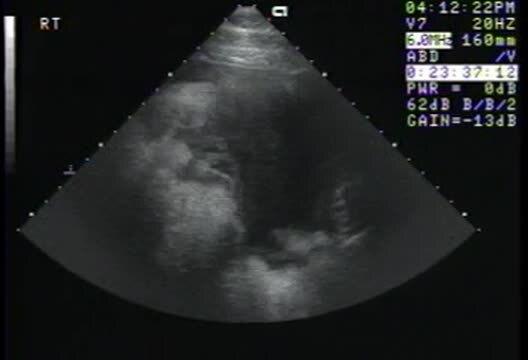

Pleuropneumonia, horse (ultrasound)

Thoracic ultrasonographic examination of a 2-year-old Thoroughbred with pleuropneumonia, demonstrating pleural effusion, pulmonary atelectasis, and fibrin accumulation on the visceral pleura.

Courtesy of Dr. Bonnie R. Rush.